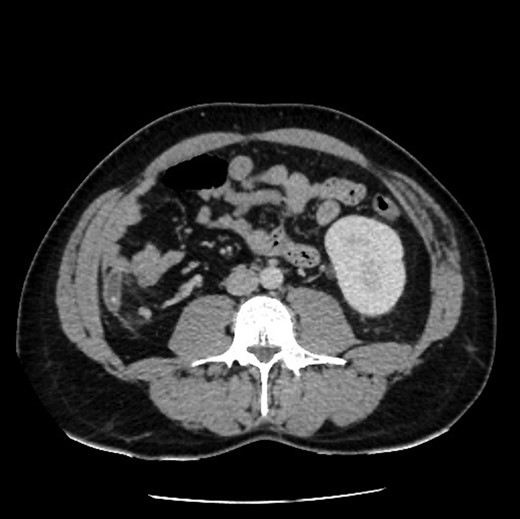

Upon review and clinically examination, the possibility of atypical appendicitis was raised due to the clinical history. Patient did not have any history of biliary colic or any epigastric pain. He was further investigated with CT abdomen which revealed the diagnosis of acute appendicitis in the right upper quadrant (Fig. 1). The atypical position of his presentation was a result of congenital right renal agenesis (Fig. 2). The appendix was lying on the right upper quadrant due to the absence of right kidney. He also had left kidney hydronephrosis and hypertrophy.

Sagittal view showing mal-descend of caecum secondary of congenital agenesis of right kidney, this resulted in subhepatic appendicitis.

Axial view showing absence of right kidney due to congenital agenesis. Appendicitis with faecolith.